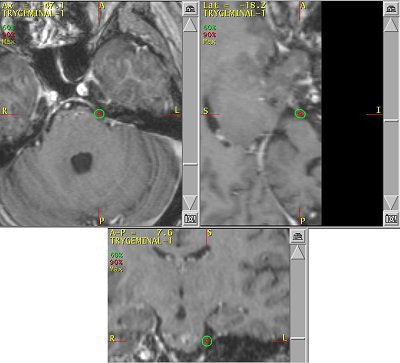

![]() |

| An example of a treatment plan for TN using a single isocenter to deliver a single fraction of 80 Gy to the TN nerve root. A single 5-mm collimator and a multiarc technique would be used to minimize dose to the brain stem. Image courtesy of Varian Medical Systems, Palo Alto, CA. |

These days, planning is done often with CT or MRI, with the latter used for planning and the former for treatment simulation. On the most basic level, all radiosurgery systems deliver high doses of ionizing radiation (65-90 Gy) to small intracranial targets via imaging guidance.

Murphy and colleagues at UCSD work with a linac system (Trilogy) and also perform gamma knife surgery. Time is one major difference between the two options in TN. A procedure with the Trilogy system takes about 30 to 40 minutes versus about two to three hours with the gamma knife, he said.

Murphy's list of linac shortcomings is, well, short. "I trained on (gamma knife). To train on a (Trilogy) system that was frameless and not proven was a hard thing to do. The dose is really high (90 Gy, four times the regular radiotherapy dose, but the same as gamma knife), and it's right next to the brain stem, so if you miss or the patient moves, you're going to fry the brain stem," he said.